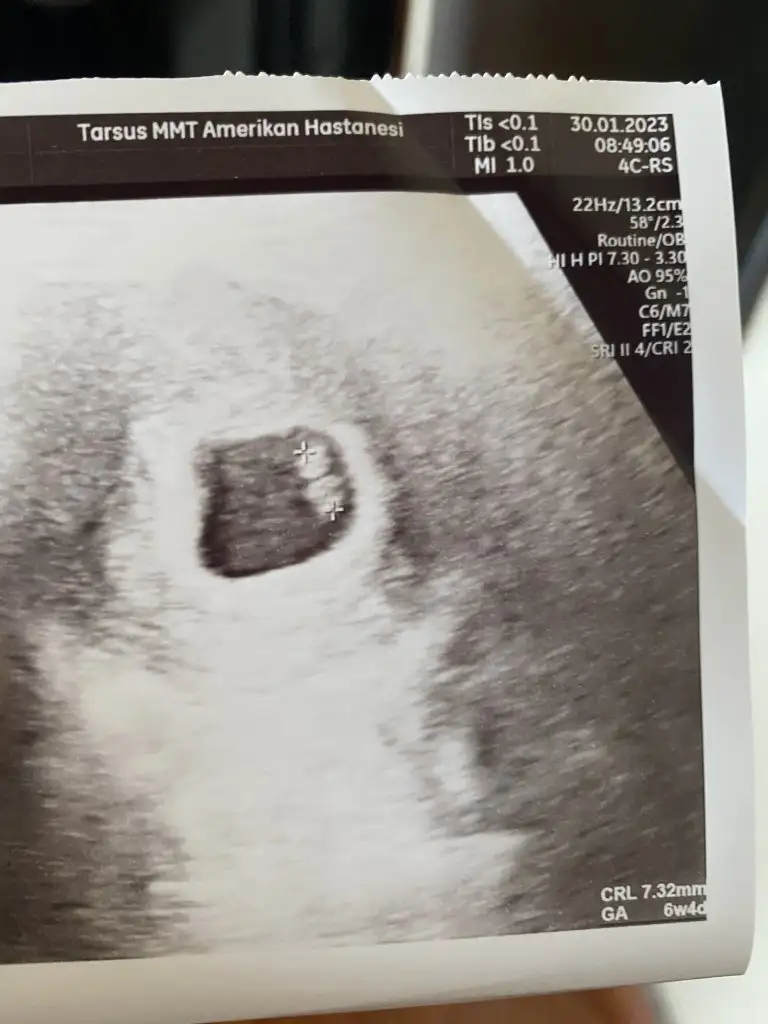

Ramzi teorisine göre kız gibi ama nedense benim içimden ilk erkek geçti hayırlısı inşallah daha küçük haftalarda var mı görüntüsü 5-7 haftalık onuda gönderin bi bakayım tekrar inan emin olamadım canım

Dokuz haftada çok tuhaf şekilde doktorumda kız olabilme ihtimali var dedi ama kesin değil bu tahmin dedi hiç bir hazırlık yapma dedi bakalım ne çıkacak sağlıklı olsun da 🤗🙏